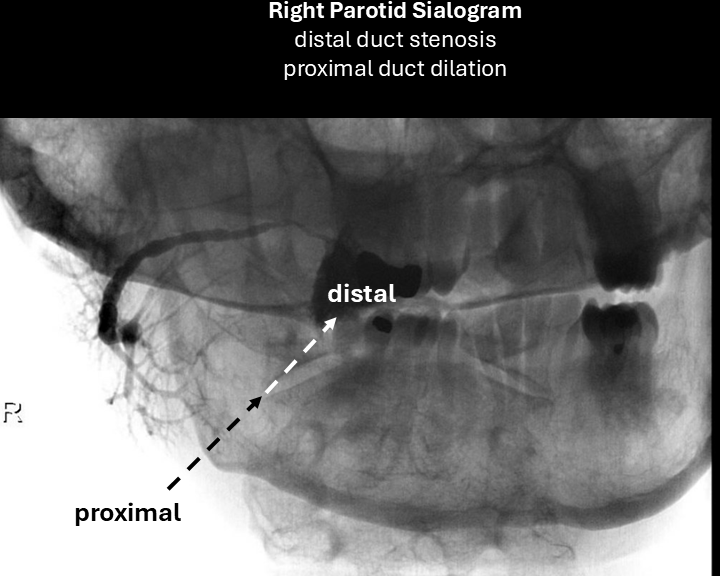

Sialogram:

Performed with 24-gauge angiocatheter - following sialogram, further dilation of duct with 22-gauge angiocatheter over 0.015-inch guidewire - unable to advance 20-gauge catheter.

right parotid sialogram 1

right parotid sialogram 2

right sialogram 3

right sialogram 4